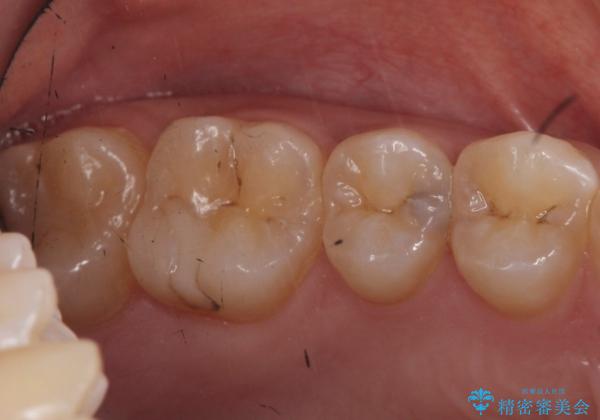

笑うと外から見える場所であるため白い詰め物での治療となりました。

- 右上5 セラミックインレー 77000円×1本費用は治療当時の料金となります

外からも確認できる虫歯だけでなく、歯の奥の面の虫歯も残さず除去しました。

残った歯の量が多かったためインレータイプでの修復となりました。